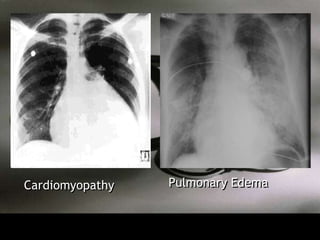

Cardiomyopathy   Pulmonary Edema

Clinical Data • CXR – Kerley’s lines : A and B – Pulmonary Edema – Cephalization – Pleural Effusions (bilateral) • EKG – Left atrial enlargement – Arrhythmias – Hypertrophy (left or right)